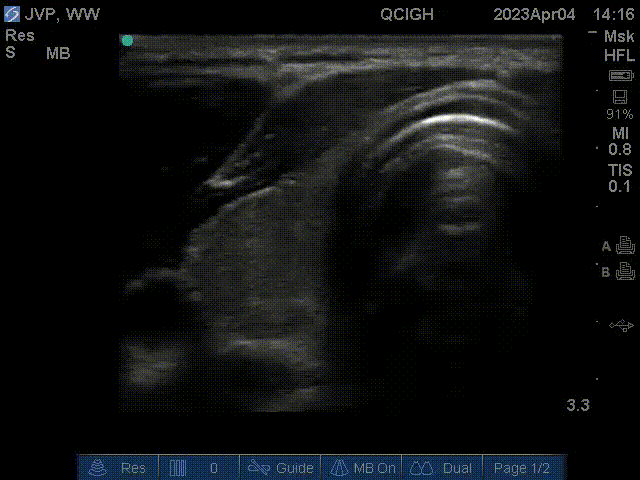

Thyroid

This scan shows the right lobe of the thyroid. The thyroid isthmus and a hyperechoic cartilaginous ring of the trachea is seen medial and anterior to the right thyroid lobe. The common carotid artery is seen pulsating medial to the right thyroid lobe.

This is a scan of the left carotid sheath. The sternocleidomastoid is overlying the internal jugular vein, which is collapsable. The common carotid artery is round and does not collapse with compression. The vagus nerve is medial to the carotid and posterior to the IJ.